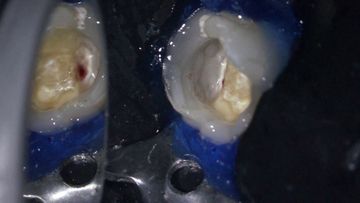

/education-service/media/default/68492/b6da3d40.jpg)

27min

Lesson

Full endodontic treatment of a lower molar with asymptomatic irreversible pulpitis

Radu Brata

Clinical Video